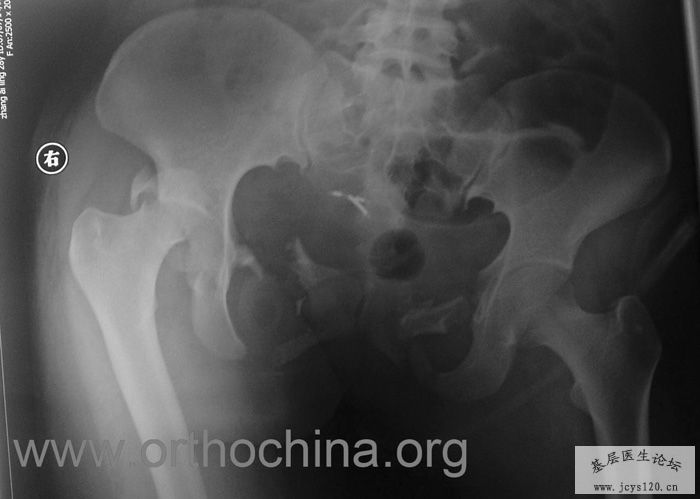

患者,女,28岁,车祸中骨盆轧伤后疼痛功能障碍1小时。查体:休克外貌,烦躁不安。头颈胸腹无异常,脊柱无异常,两下肢血供及感觉正常。骨盆挤压分离试验阳性。阴道、尿道、直肠、腹内脏器无损伤。住院后抗休克、骨牵引及对症治疗1周后,行前后联合入路手术。股骨头骨折复位后用可吸收螺钉固定,骶髂关节、髋臼前后柱、对侧耻骨上下支用骨盆重建钛板固定,术中出血1200ML,手术时间8小时。部分图片如下: